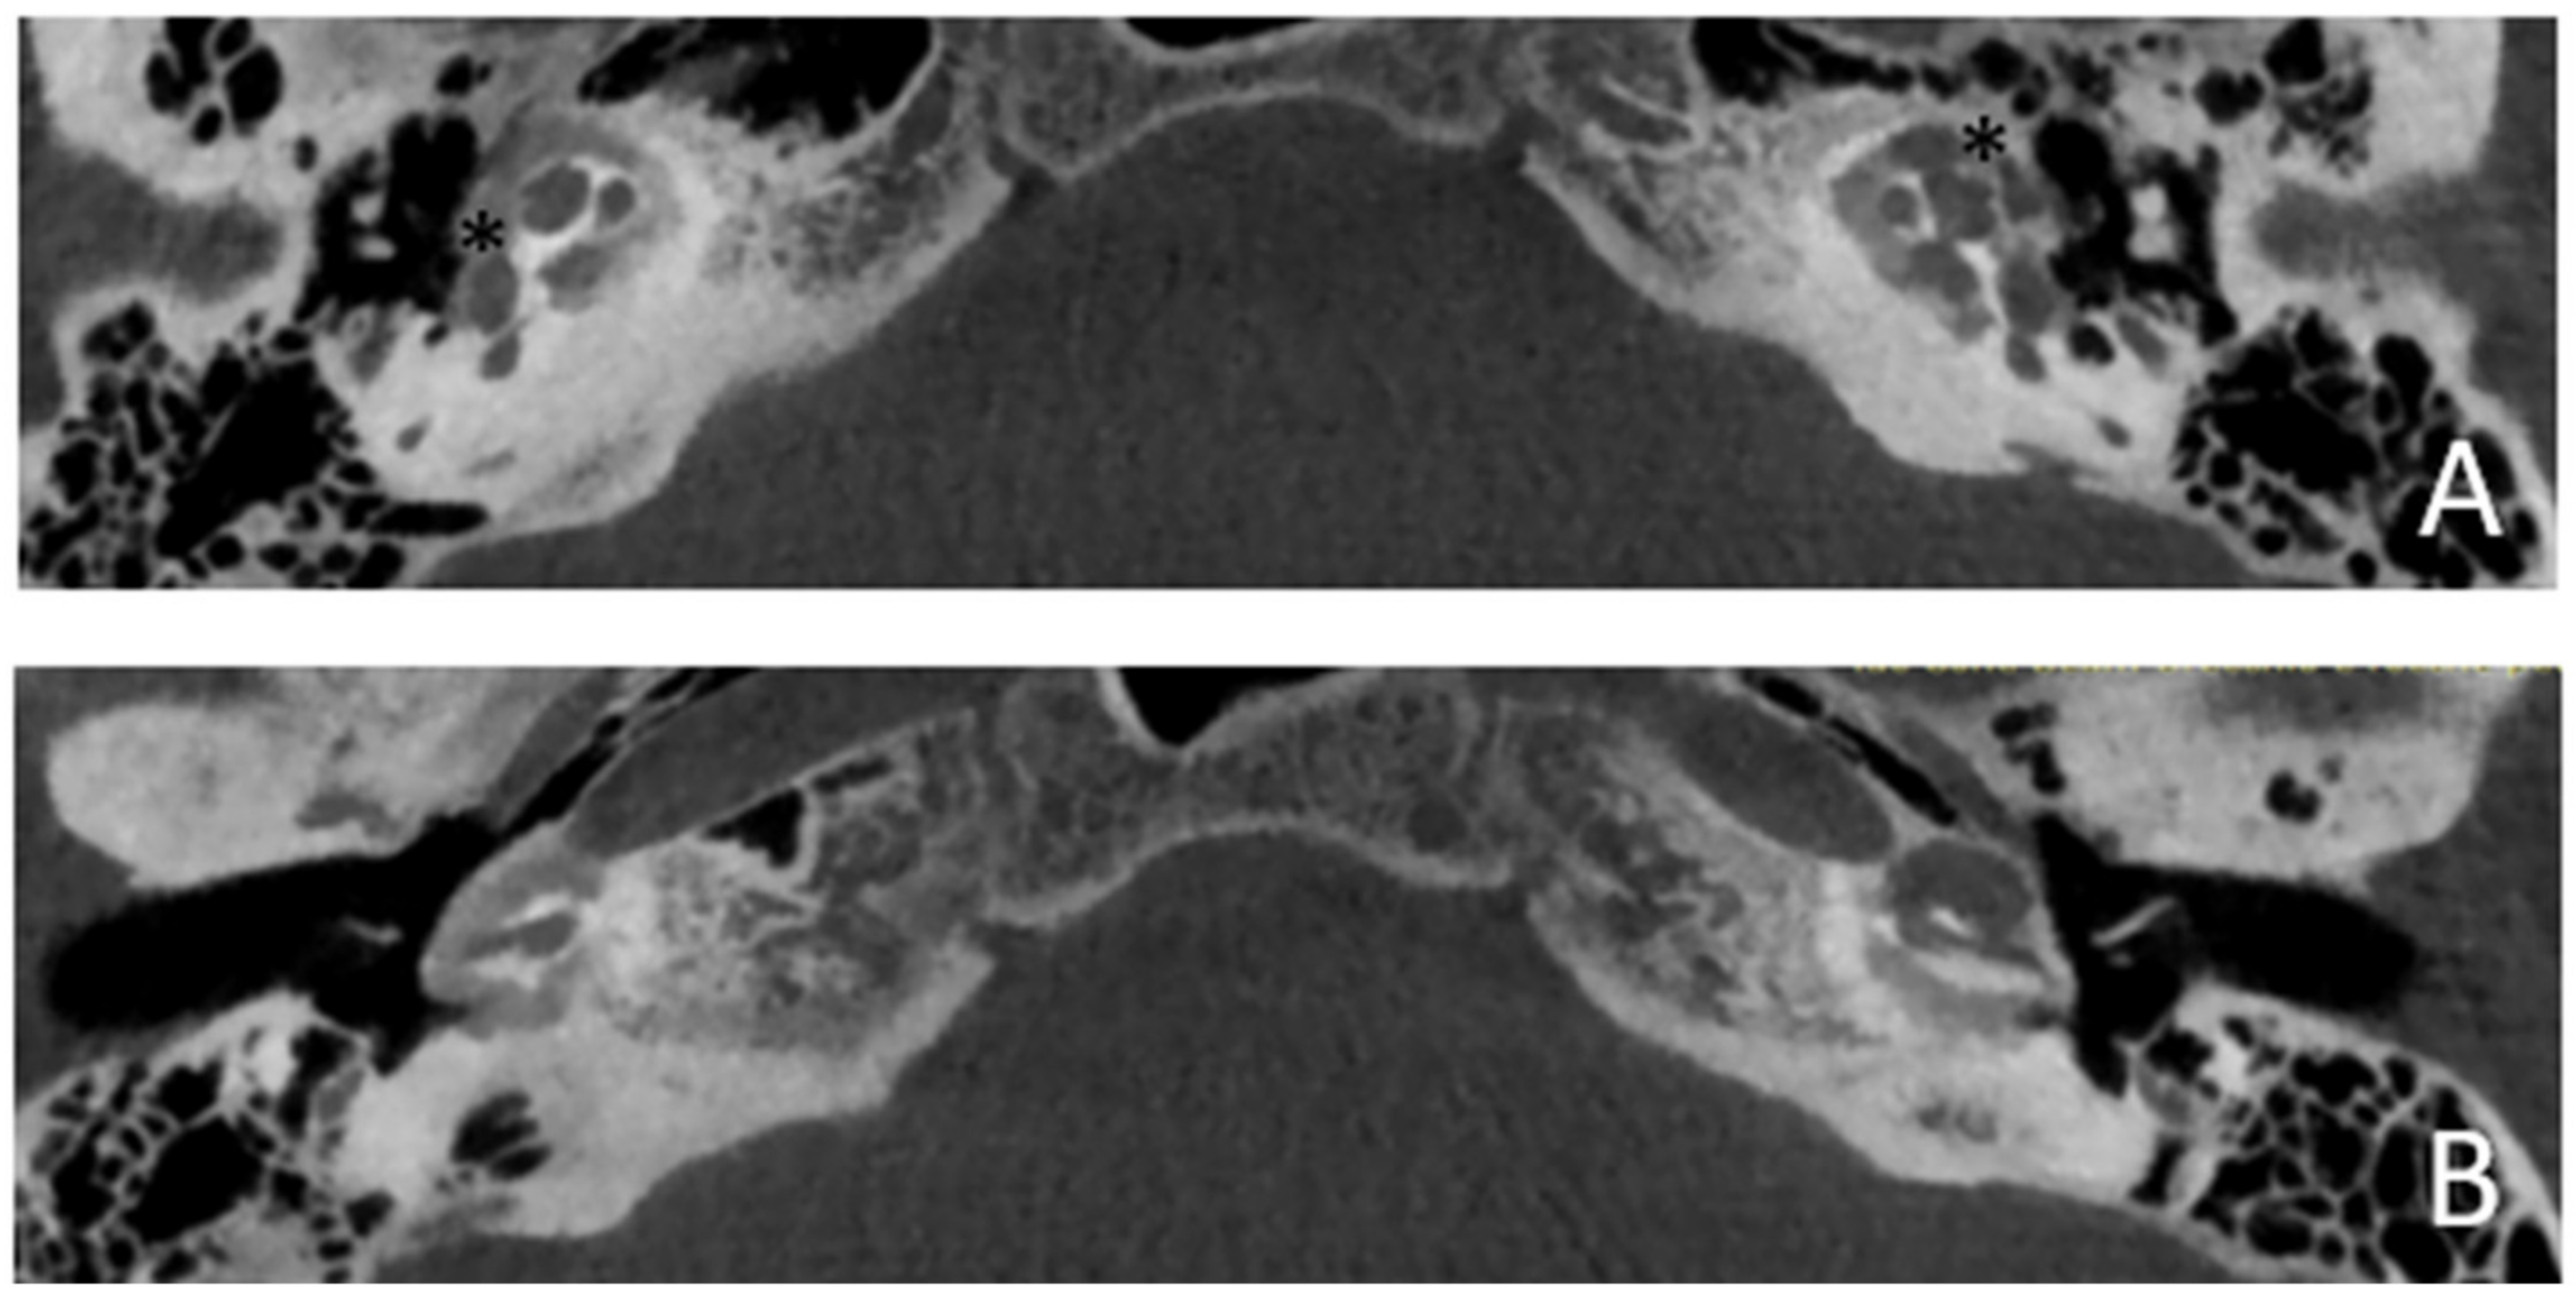

Within a few years, both ears showed a worsening of bone threshold to SNHL bilaterally. In 2017 (27 years since diagnosis) she developed profound SNHL with left-sided anacusis and underwent cochlear implantation in the left ear. CT and MR images showed a large cavity around the basal turn of the cochlea and massive osteorarefaction around the cochlea (‘double ring’ sign). The cavity appeared to contain cerebrospinal fluid but did not communicate with the cochlear lumen (Figure 1 and Figure 2).

Figure 1.

CT images of patient #1 with osteogenesis Imperfecta. (A,B), right side in axial plane. (C,D), right side in coronal plane. (E,F), left side in axial plane. (G,H), left side in coronal plane. A pericochlear cavity is visible in all figures; arrows indicate its origin from the IAC. Asterisks indicate extension of osteorarefation into the cochlea.

Figure 2.

MR image of patient #1 with osteogenesis Imperfecta. MR cisternography showing the fluid-signal in the newly formed cavity (white asterisk).